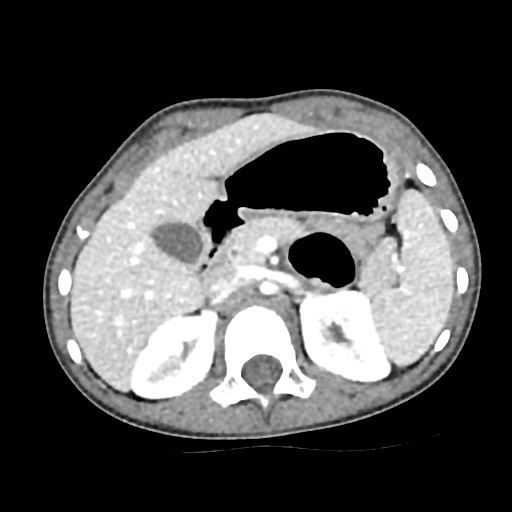

Se realiza posteriormente un TC abdominal (Figura 2) para completar información. Debido a que no se encuentra ninguna lesión que justifique el cuadro obstructivo (ni intrínseca ni extrínseca), se solicita una intervención quirúrgica urgente para la visualización abdominal mediante laparoscopia exploradora. En la intervención, se localiza una brida congénita yeyunal como causa de la obstrucción, que es resecada con éxito.

| Figura 2. TC abdominal. Atrapamiento duodenal con dilatación proximal. La brida no se visualiza como tal, pero sí su efecto compresivo |